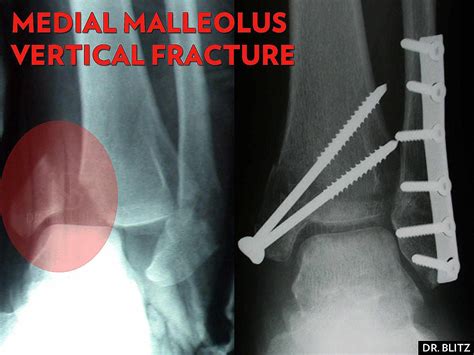

Medial Malleolus